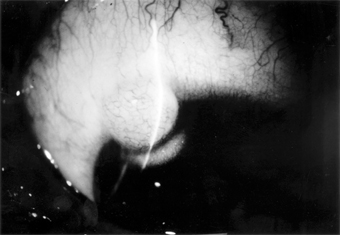

Nevus (Figure 5-26)

One-third of melanocytic nevi of the conjunctiva lack pigment. Over half have cystic epithelial inclusions that can be seen clinically.

Figure 5-26

Figure 5-26: Conjunctival nevus. Note sharp borders.

Histologically, conjunctival nevi are composed of nests or sheets of nevus cells. Conjunctival nevi, like other nevi, rarely become malignant. Many are excised because they are disfiguring.

Pigmented conjunctival nevi must be distinguished from primary acquired melanosis of the conjunctiva. The latter occurs later in life (after the third decade), is usually unilateral, tends to wax and wane in degree of pigmentation, and, depending on the degree of cellular atypia, has a risk of becoming malignant ranging from nil to 90%.